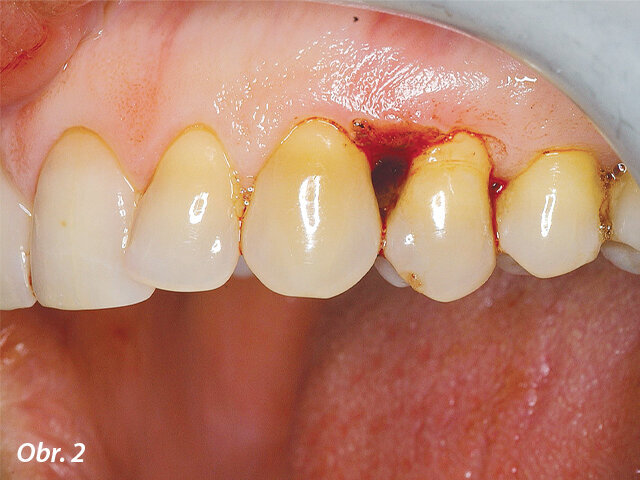

Jak je patrno z obrázku 1, pacientka se dostavila do mé ordinace s lokalizovanou hutnou hyperplastickou oblastí dásně, která byla potvrzena klinickým vyšetřením. 31letá pacientka měla elegantní oblečení a čisté, dobře udržované ruce a nehty. Stěžovala si, jak je těžké danou lokalizovanou oblast čistit a popisovala, že snaha o vyčištění bolí a způsobuje krvácení, především při použití dentální nitě. Došlo k narušení kontinuity hladkého vzhledu gingivy, díky čemuž vypadal její povrch nerovně a esteticky rušivě.

Hutná hyperplastická tkáň interproximálně mezi zuby 23 a 24. Hyperplasticky změněná tkáň omezovala přístup do interdentálního prostoru, v důsledku čehož nebyla pacientka schopna provádět v inkriminované oblasti řádnou ústní hygienu.